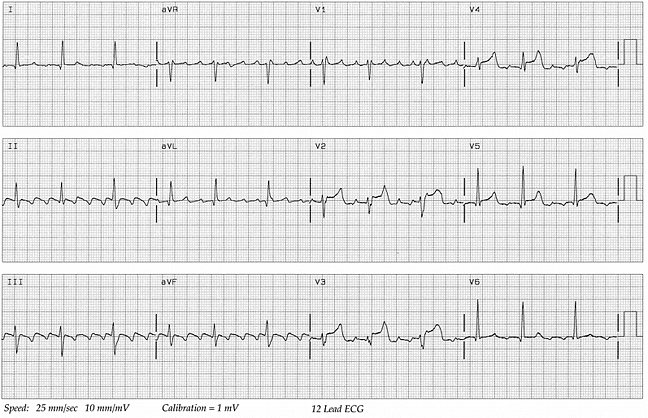

Стандартная электрокардиограмма в 12 отведениях, показывающая фибрилляцию предсердий с контролируемой частотой сокращения желудочков

Рисунок 1. Стандартная электрокардиограмма в 12 отведениях, показывающая фибрилляцию предсердий с контролируемой частотой сокращения желудочков.